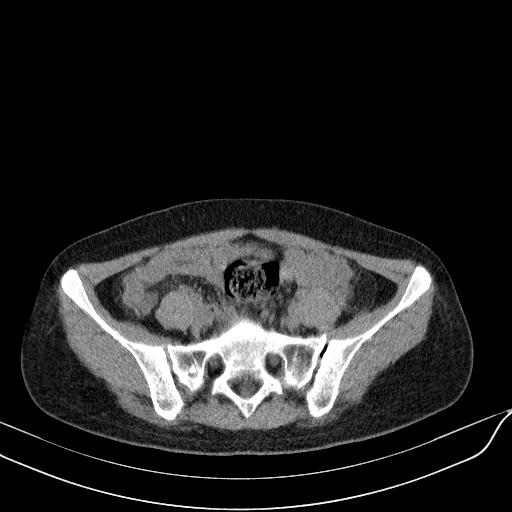

标题: CT23965:无外伤史,下腹痛 [打印本页]

标题: CT23965:无外伤史,下腹痛

肠道未准备,继续往下扫,乙状结肠占位不排除。建议钡灌或结肠镜检查。

乙状结肠占位不排除

未见明显异常改变,做个气钡双重造影除外一下结肠病变,无外伤史为啥不常规喝泛影葡胺水对比剂再扫ct呢?

肠道肿瘤,建议行钡剂灌肠检查。